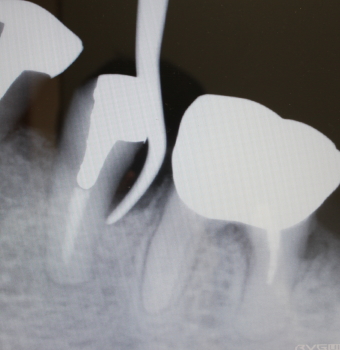

骨補填剤充填後のX-ray

2016年07月21日撮影